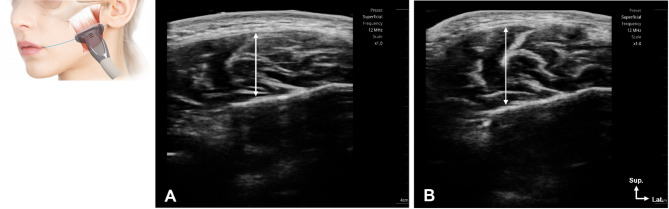

Methods: Thirty-four male wrestlers (Pro: 13; Npro: 21; age: 26.7 ± 9.3 years) participated in this comparative cross-sectional study. Bite force was assessed using pressure-sensitive films, and masseter muscle thickness was measured via ultrasonography. Group comparisons and asymmetry analyses were conducted using appropriate statistical methods.

Results: Professional athletes exhibited significantly greater bite force (1071.7 ± 380.2 N) than non-professionals (856.9 ± 363.1 N, p = 0.032). Masseter muscle thickness was also higher in professionals (15.6 ± 1.5 mm right, 15.9 ± 1.4 mm left) than in non-professionals (13.6 ± 1.3 mm right, 13.8 ± 1.2 mm left, p < 0.01). Bite force asymmetry was more pronounced in professionals (70.1 ± 29.3 N vs. 43.1 ± 21.8 N, p = 0.017).